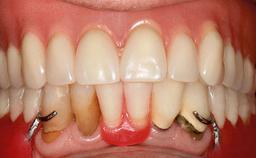

Surgical treatment of a 67-year-old male patient exhibiting an extended edentulous space in the anterior maxilla after the removal of three hopeless incisor teeth.

The case concludes with the presentation of the final prosthesis and the esthetic outcome, demonstrating stable soft tissue conditions and stable bone crest levels at the 3-year follow-up.